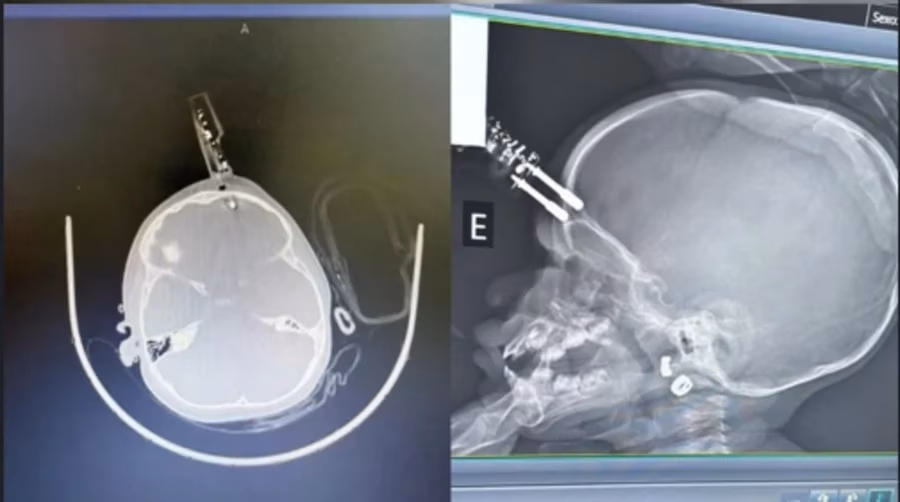

Uma criança de 1 ano passou por uma cirurgia de emergência na terça-feira (13/1), em Divinópolis (MG), após cair da cama e ficar com um carregador cravado na testa. Segundo os médicos, a menina permanece em observação e, até o momento, não há sinais de sequelas neurológicas.

De acordo com o neurocirurgião Bruno Castro, responsável pelo atendimento, a mãe da paciente tinha ido ao banheiro quando o acidente ocorreu. A menina segurava o carregador na mão ao cair da cama e acabou com o objeto cravado na cabeça.

A vítima foi encaminhada à sala de cirurgia, onde passou por procedimentos de limpeza, retirada do objeto, lavagem, fechamento e reconstrução da área atingida. A equipe médica segue monitorando o quadro da criança após o procedimento.